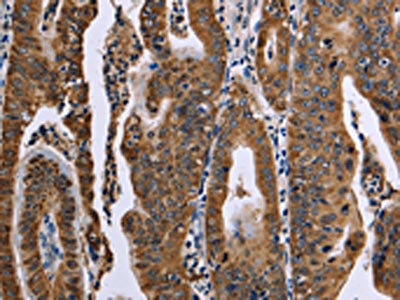

The image on the left is immunohistochemistry of paraffin-embedded Human gastric cancer tissue using CSB-PA993404(FAF1 Antibody) at dilution 1/50, on the right is treated with synthetic peptide. (Original magnification: ×200)